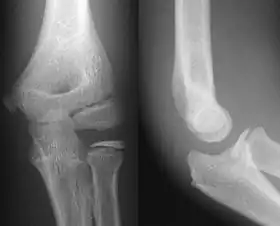

![]() AP and lateral elbow X-ray | |

- Elbow - AP and Lateral. Radial head projections available on request

Lateral projection

Anteroposterior projection

Left elbow by 30 degrees internal oblique projection

Left elbow by 30 degrees external oblique projection